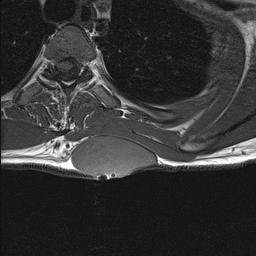

Neurofibrosarcoma Axial MRI NeurofibromatosisNeurofibrosarcoma MRI